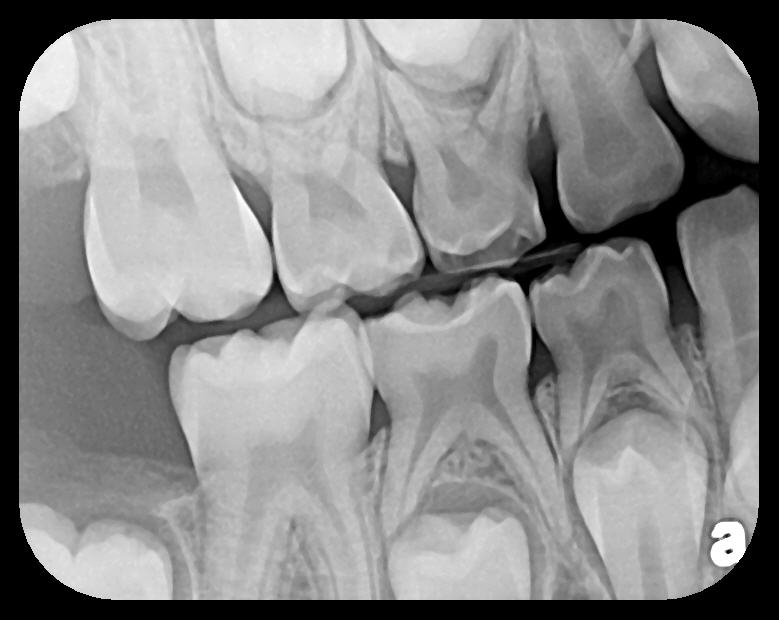

PSP sensor technology offers many advantages to the clinician in patient retention and workflow. The most important consideration is patient comfort and cooperation. PSP sensors are wafer-thin and flexible to allow placement in positions to capture third molar images without gagging or pain. The larger surface area of the most popular no. 2 size PSP sensor allows images of more dental anatomy (Figure 3); therefore, fewer exposures are necessary to create a full-mouth radiographic series. Their flexibility allows placement around tori and exostoses.1,9-12 The bite blocks, stabilizers, BW tabs, and positioning rings that were used for film radiographs will easily accommodate PSP sensor placement.

Some representative radiographic PSP images are exhibited here for demonstration of the anatomy and pathology that can be visualized with this technology. Many of these images would not have been possible if HW technology were used (Figure 3 through Figure 8).

As displayed here, the 2D radiographic images in Figure 3 through Figure 8 can alert the clinician to the need for a further 3D CBCT analysis to properly ascertain the anatomy and extent of the pathology that is initially visible in the intraoral radiographs. Proper treatment or referral to the appropriate specialty practice can follow.5,6 No. 2 PSP radiographs, when used in a conventional full-mouth series of radiographs on a patient with a relatively complete dentition, will routinely allow visualization of the anatomy of third molars, mandibular canal, maxillary sinuses, full dental root morphology, and bone anatomy beyond the apices2,16,17 (Figure 9 and Figure 10).

Fig 3. Two PSP PA radiographs of mandibular teeth showing: left, the initial view

of molar area and suspected pathology surrounding impacted tooth No. 32; center,

subsequently exposed PA radiograph, placed more distally, demonstrates extent

of large cyst as well as entire tooth and root No. 32. Proper alert as to presence

of suspected cyst and appropriate referral for 3D CBCT study and surgical

enucleation was given to the patient. Right: Same radiograph as on the left, but

with lighter superimposed outline of the area that would be visible using an HW

sensor rather than a PSP sensor. The small area of pathology is likely obscured

because it is visually overlaid by the root of tooth No. 31. Neglect of this significant

pathology may have resulted.

Figure 3